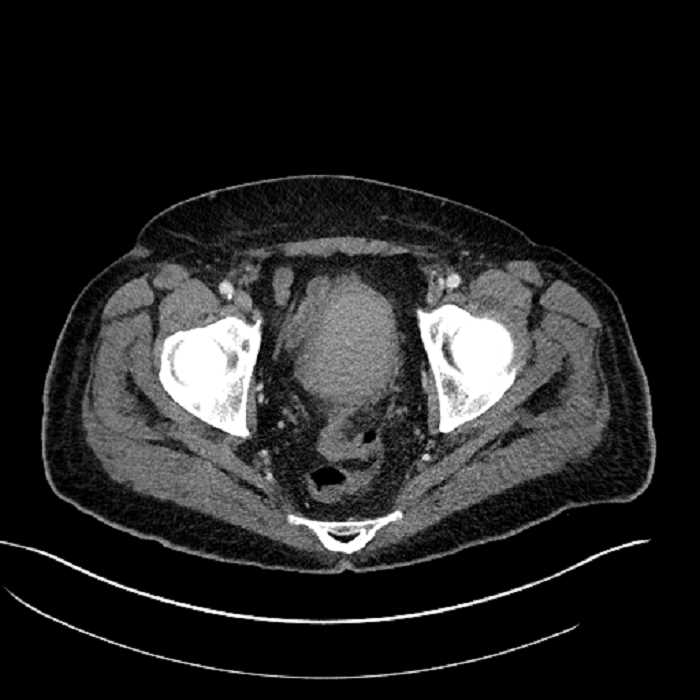

• Mild mural thickening of a segment of the sigmoid colon with adjacent fat stranding and a 1.5 cm fluid and gas collection along the tip of an inflamed diverticulum

• Loss of the normal fat plane between this collection and adjacent loops of small bowel, which demonstrate mural thickening

• No bowel obstruction

• High grade stenosis of the left common iliac artery, with the left internal and external iliac arteries remaining patent

Acute sigmoid diverticulitis complicated by a small contained perforation and a large abscess in the right hepatic lobe. Additional small subcapsular abscesses along the anterior margin of the left hepatic lobe.

Additionally, loss of the normal fat plane between the peridiverticular collection and adjacent thickened loops of small bowel raises the potential for an enterocolonic fistula.

High grade stenosis of the left common iliac artery. The left external and internal iliac arteries are patent.

Hepatic abscess showing the double target sign with low density internally surrounded by a thin inner enhancing rim (red arrow) and ill-defined outer low density rim (yellow arrow). Blue arrow indicates an internal septation. Red arrows: additional smaller subcapsular abscesses. Red arrow: focal contained perforation associated with diverticulitis.